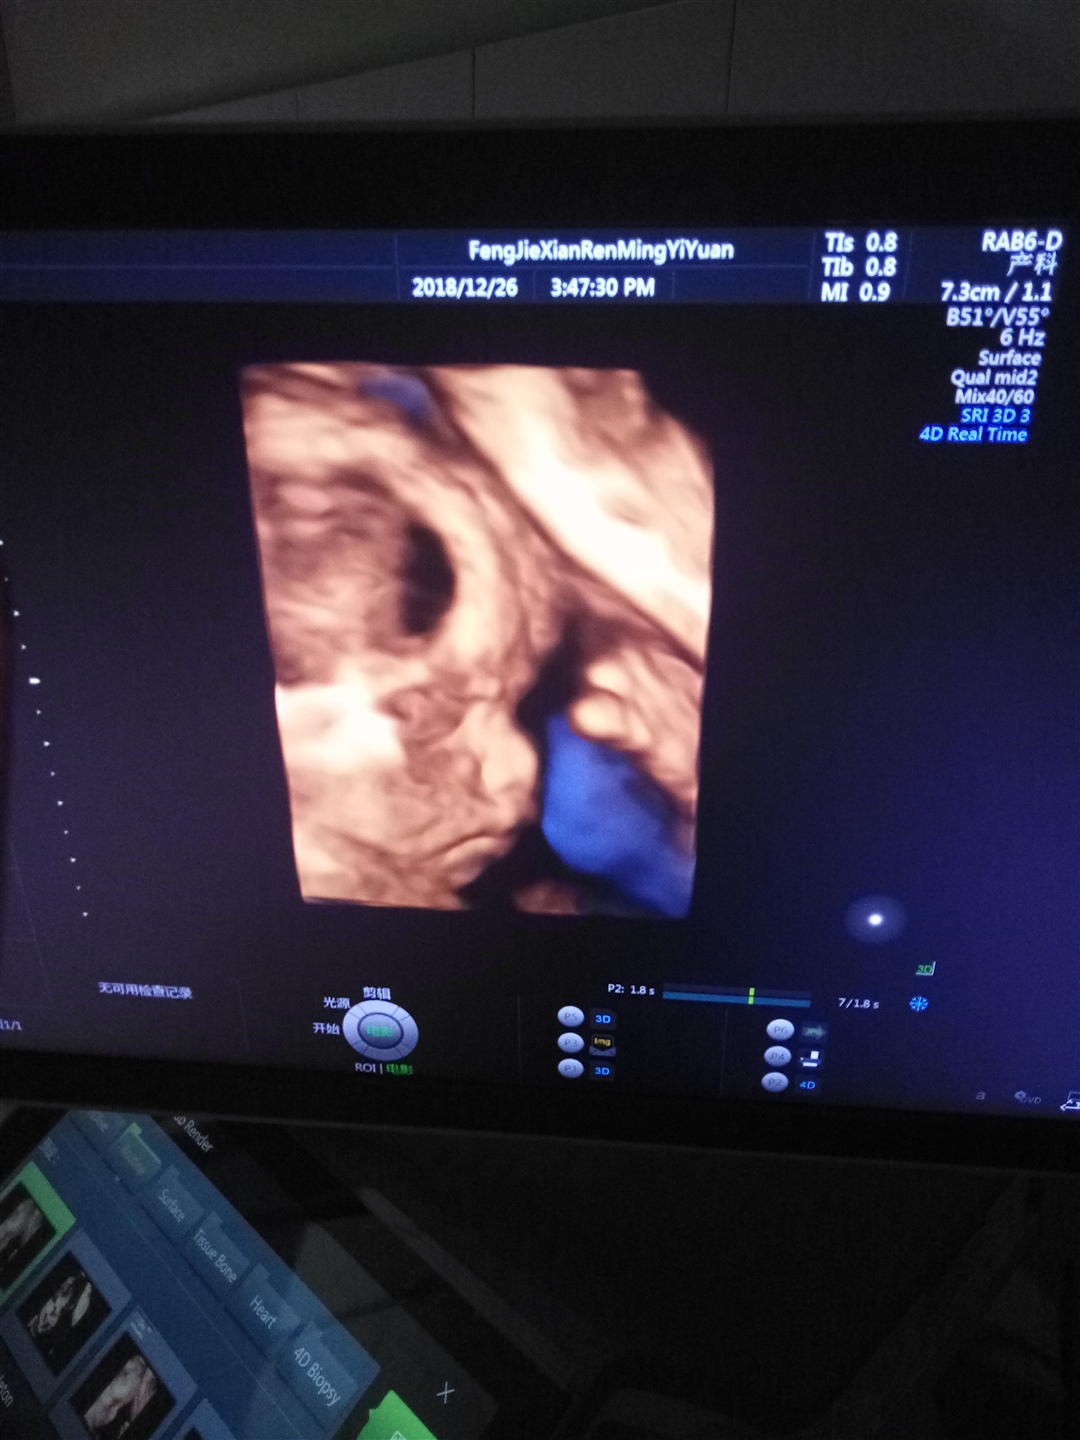

按彩超单的2还是男孩…